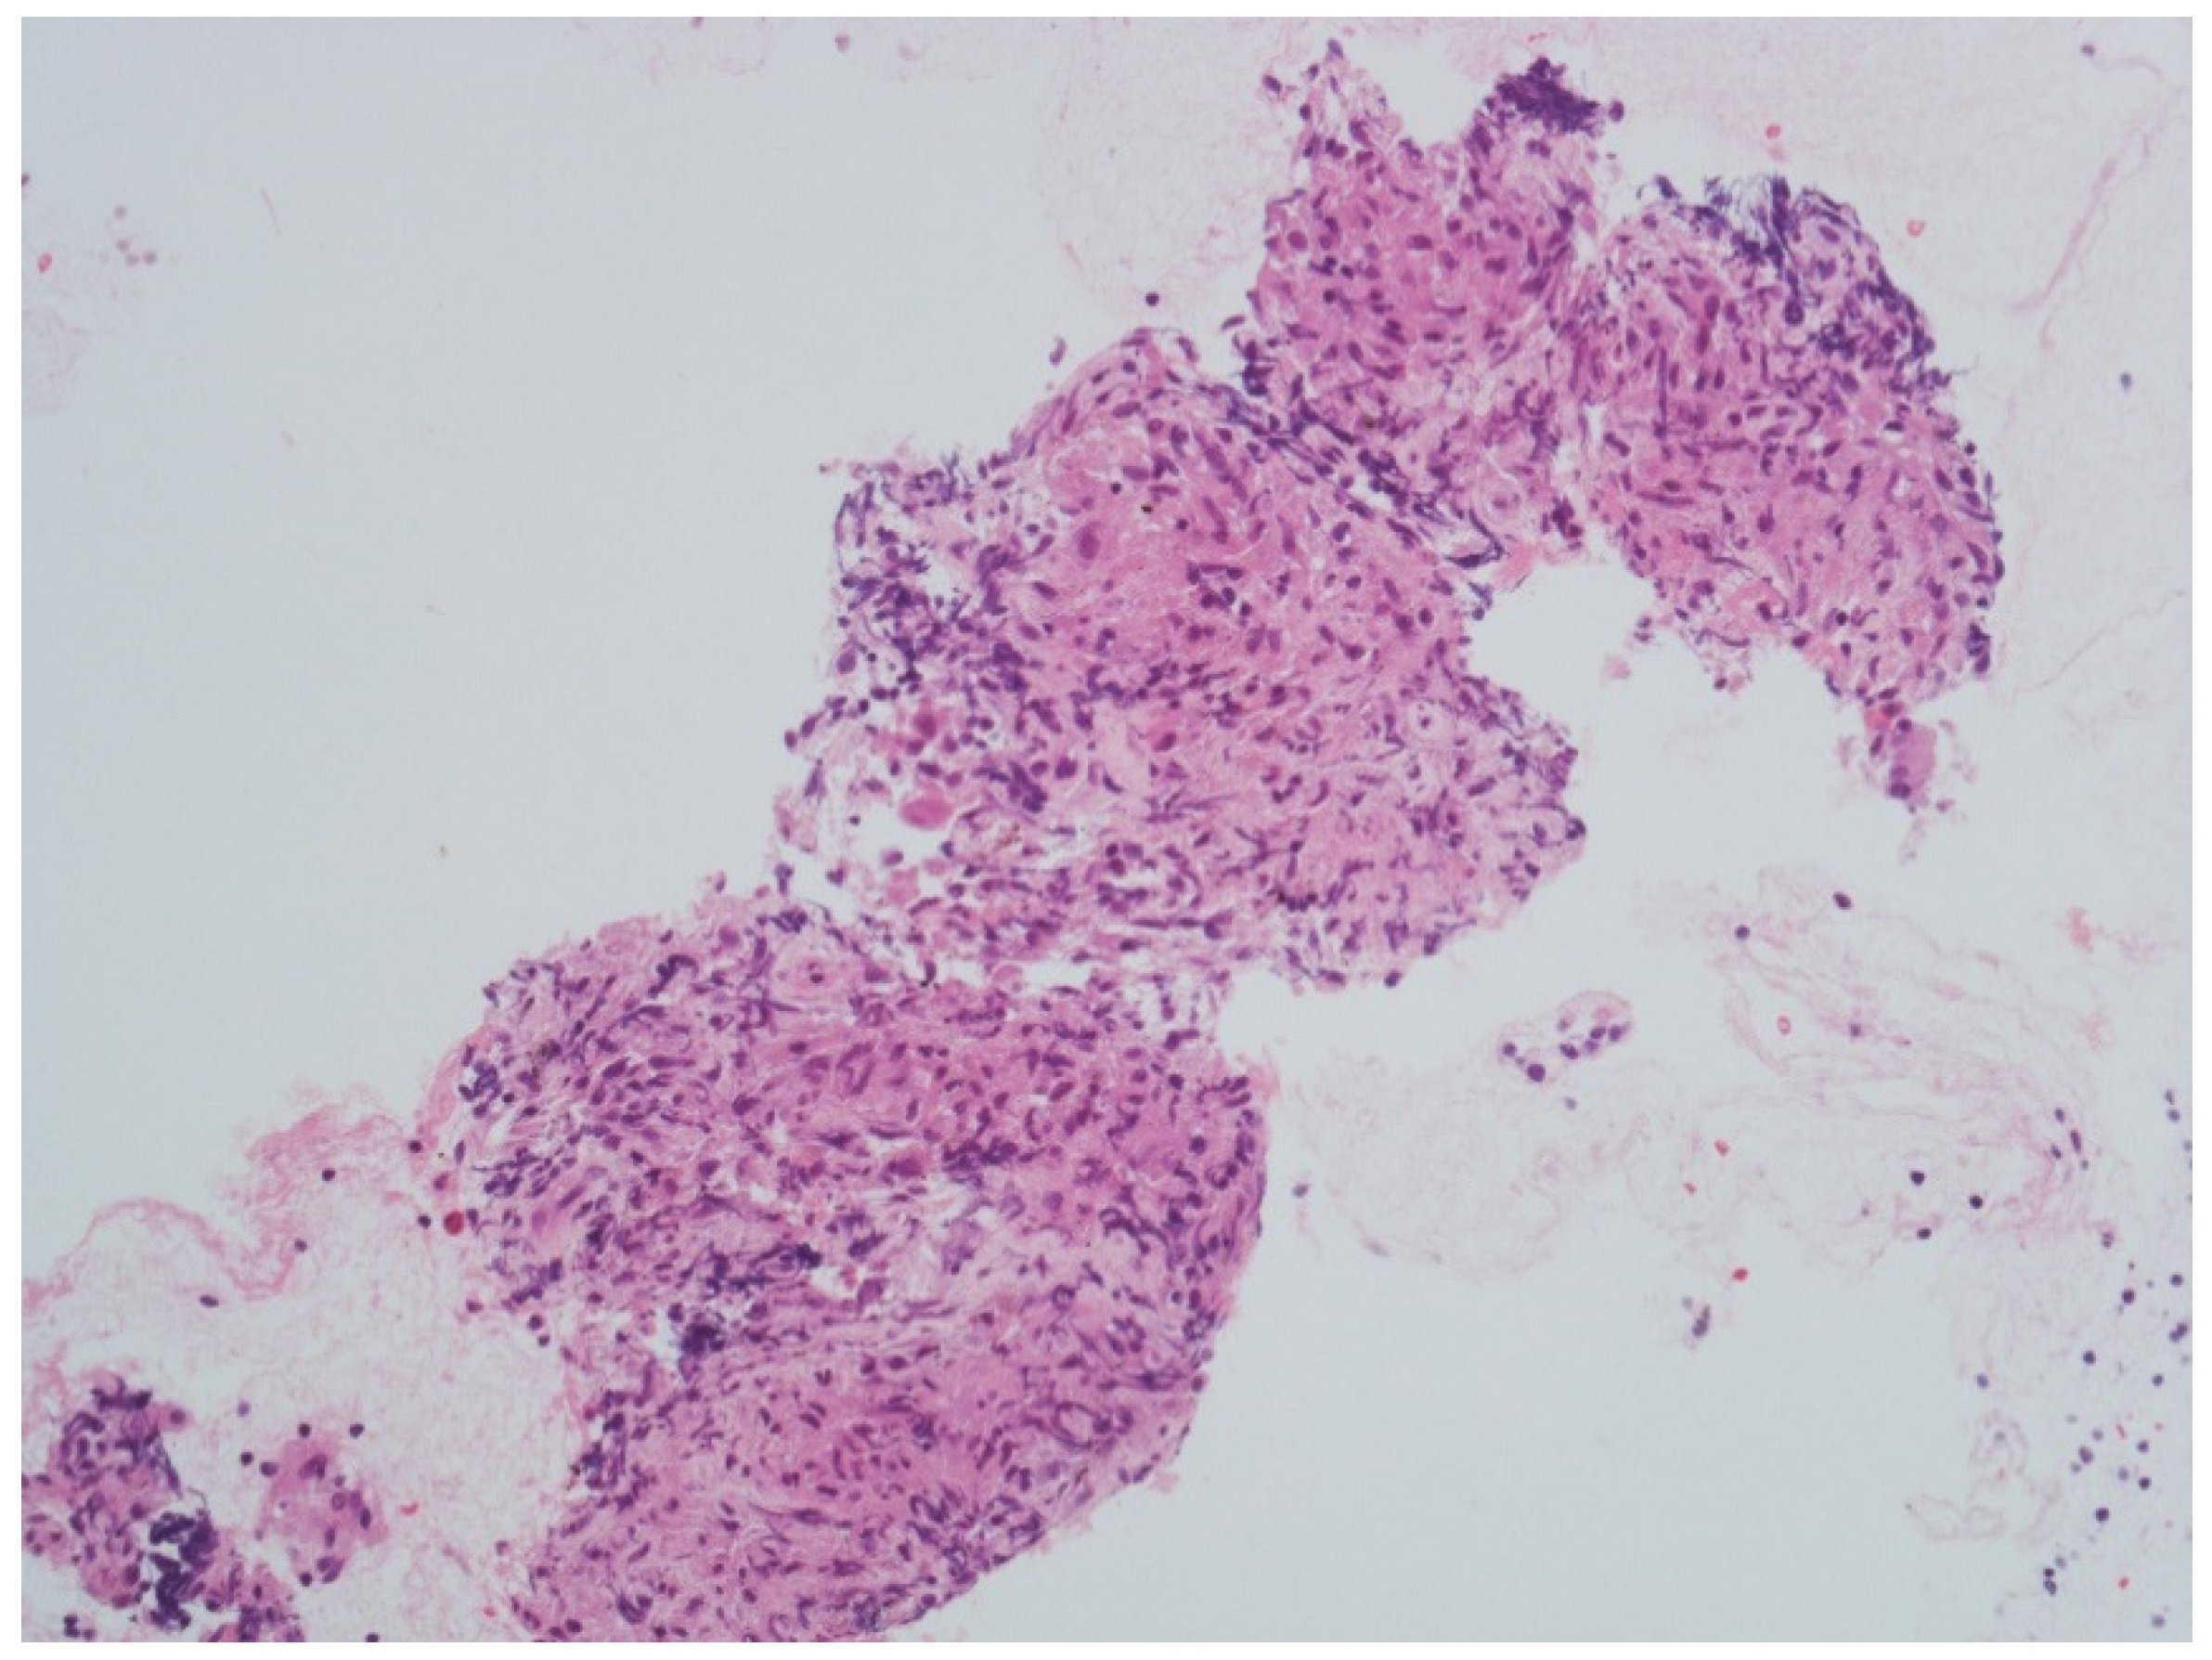

After a week, she presented with left peripheral FNP, bilateral hearing loss, limitation in left gaze, expression of left sixth cranial nerve palsy, and liquid dysphagia. The examination confirmed the presence of cranial multineuritis. Following readmission, a lumbar puncture was performed with cerebrospinal fluid (CSF) analysis showing a slight increase in cell count (17 cells/mm3—monocytes), normal protein (31 mg/dL), and glucose level (70 mg/dL); malignant cells were not seen on cytology. The PET scan showed multiple supraclavicular, paratracheal, epiaortic, paraesophageal, and parahilar adenopathies with a high metabolic component. Serological tests, including ANCA, ANA, HIV antibody test, tuberculosis, and B.Borrelia serology, were negative, but the sedimentation rate of the erythrocytes (ESR) was 24 mm/h. Flow cytometry was not performed. Based on clinical presentation and exam results, the suspect of a granulomatous disorder was made, and corticosteroid therapy (1 mg/kg of prednisone–55 mg/day) was started with a partial clinical benefit over four days. A needle biopsy was performed via bronchoscopy and showed epithelioid macrophages in granulomatous aggregation to characterize the lymph node alterations (Figure 2).

Figure 2. Parahilar lymph node biopsy showing epithelioid macrophages in granulomatous aggregation (courtesy of Professor R. Boldorini Division of Pathology, Department of Health Science, University of Piemonte Orientale (UPO), Novara, Italy). Scale bar: 100 μm (40× magnification).